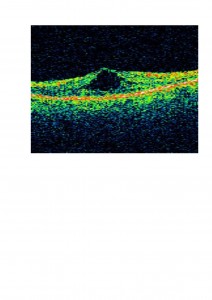

Os presentamos el caso de un paciente atendido en nuestra clínica. Presentaba una aguudeza visual OD 0,3 y OI 0,1 , con cataratas en ambos ojos (mostrada en la foto anterior). En el fondo de ojo presentaba buena coloración de las papilas y en la OCT un edema macular cistoide como os mostramos.

En este paciente decidimos tratar el edema macular cistoide previo a la cirugía de cataratas con acetazolamida oral debido a que muy probablemente iba a empeorar tras la cirugía. En la OCT os mostramos cómo disminuyó el edema: